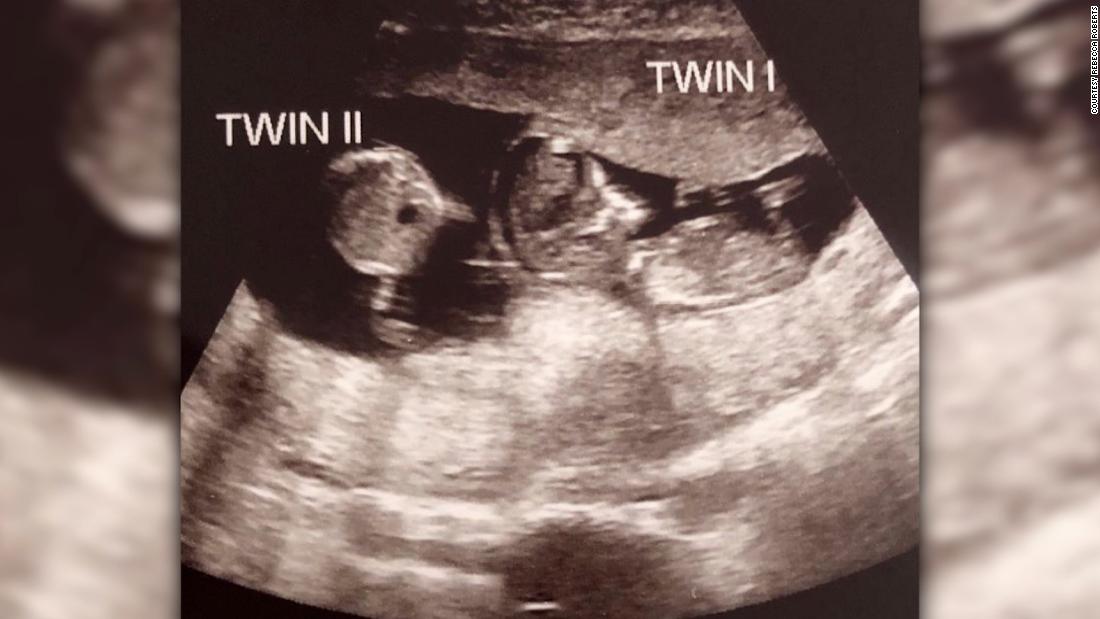

Hình ảnh siêu âm thai kỳ của Rebecca và sự xuất hiện của bào thai thứ hai. Ảnh: CNN

Kết quả siêu âm ở tuần thứ 7 và thứ 10 cho thấy Noah (tên của em bé thứ nhất) phát triển bình thường trong bụng mẹ và không hề có dấu hiệu của "sự sống thứ hai". Tuy nhiên, lần siêu âm ở tuần tuổi thứ 12 của Noah cho thấy có một bào thai mới được hình thành. Đó là Rosalie, em song sinh của Noah.

Các bác sĩ cho biết, Noah và Rosalie được thụ thai cách nhau chỉ 3 tuần. Trong quá khứ chỉ mới xuất hiện những trường hợp phụ nữ đã thụ thai thêm sau 10 ngày mang thai lần đầu tiên. Các bác sĩ cũng chỉ ra, dù được thụ thai sau nhưng đứa trẻ thứ hai vẫn đang phát triển rất tốt trong bụng mẹ.